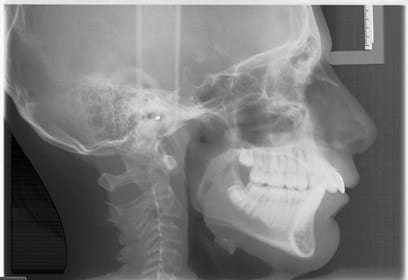

An overbite or overjet, also known as a Class II malocclusion, is a common dental problem that occurs when the upper jaw protrudes too far over the lower jaw or when the upper front teeth are angled too far forward.